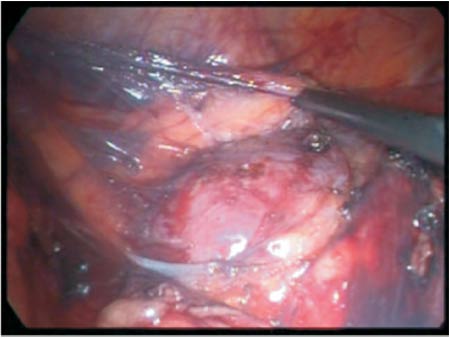

The patient was placed in the left half-lateral decubitus position with pads to relieve the pressure over some areas. Two 10mm trocars and two 5mm trocars were used, one at the umbilicus where it was inserted a 30o optical the other 10mm was inserted 12 cm from this one in the middle line. One 5 mm trocar was inserted at the midline between the right anterosuperior iliac spine and the umbilicus and at last a 5 mm trocar is inserted two fingers below the furcula to move the liver. The right colon and duodenum were repelled to the midline and the kidney with its perirenal fat was identified. The fat was removed from the lateral part (Figure 3) until the capsule could be seen, remaining just slightly close to the hilum. At this moment, the patient was placed in Tredlemburg position in order to be investigated the correct position of the kidney that was going to be fixed. Three 2.0 polypropylene threads were inserted into the lateral border of the kidney and they were temporarily fixed into the lateral abdominal wall. Another suture of the same thread was passed through the upper pole of the kidney and afterwards into the infrahepatic peritoneum which was tied up to the portion that was more proximal to needle with a second polymer clip (Figure 4). Afterwards the remained threads that were inside the cavity were passed longitudinally through the psoas muscle (Figure 5) avoiding the genitofemoral nerve, and they were tied as the previous one. The fixation was tested with the operative table placed in anti-Trendlemburg position, the hemostasis was checked and a laminar drain was left in the abdominal cavity.

Figure 5 - Needle longitudinally passed through the iliopsoas muscle, in order to avoid the cutaneous branch of the genitofemoral nerve.